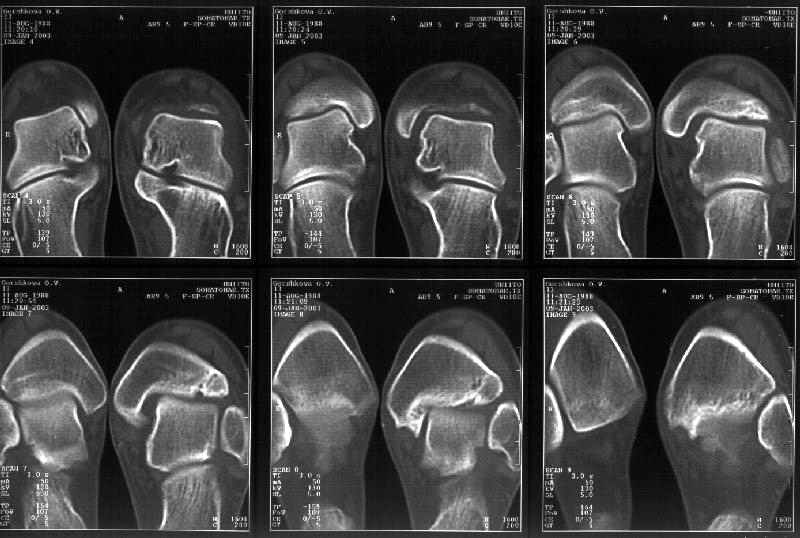

Здесь 4 среза, начиная от основания лодыжки и проксимальнее. Где, по Вашему мнению, проходит линия перелома, отделяющая переднюю часть внутренней лодыжки от большеберцовой кости? Заранее спасибо.

Я пометил линию перелома черной линией.

К сожалению на последних присланных срезах КТ нет более низкого, через таран, среза, который был на прежнем майле. На XR я попытался показать

стержень внутри сустава и то как он раскрывает пространство между тараном и мед. малеолом.

Сегодня пациентке сделали сравнительную КТ. А ксиальные и Фронтальные срезы приложены. Ваше мнение?

Фронтальные

Аксиальные

На КТ я попытался изобразить скромными своими способностями (А)- место перелома, (С)- нормальный суставной зазор меж тараном и тремя его маллеолами. (В)- образовавшийся в результате перелома широкий раза в три зазор, позволяющий, по-моему, сублюксацию тарана при ходьбе. В свете данных КТ, критически важных, я бы предложил вертикальную остеотомию места перелома

задне-внутренним подходом и фиксацию мед. маллеола прижатым к тарану с помощью тонкого compression screw. После этого гипсовый сапожок и немедленное расхаживание ноги.